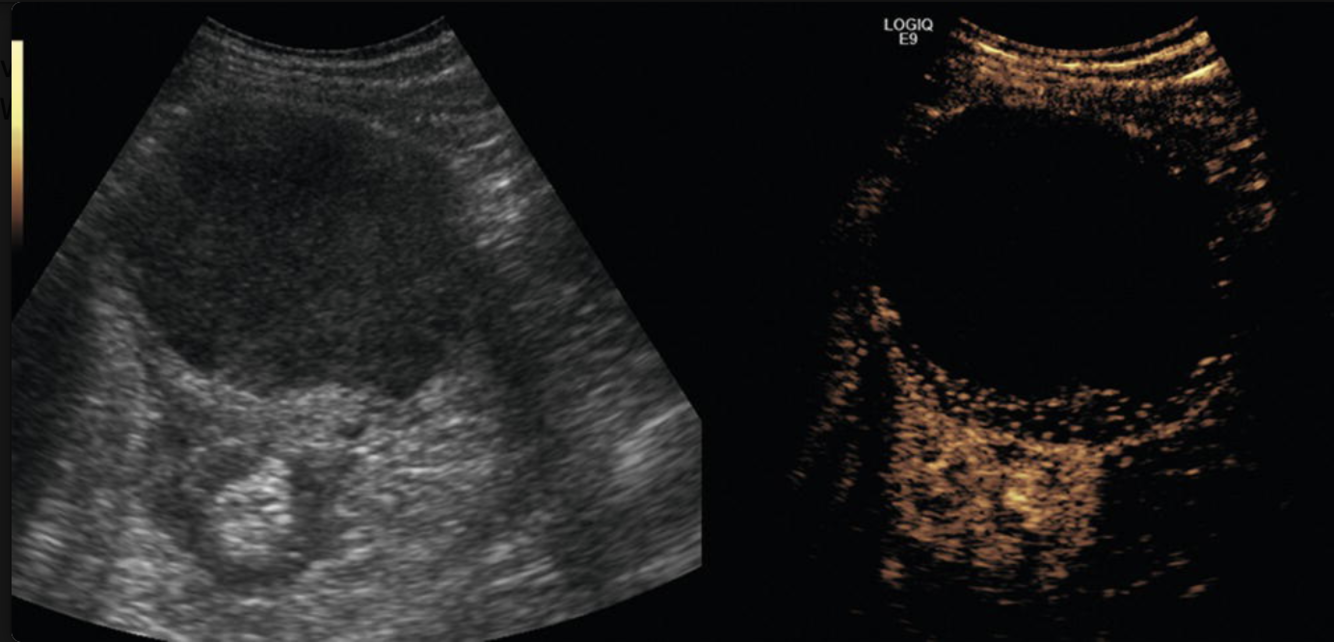

What is the benefit of tissue harmonics (seen here on the R)?

Why is CEUS useful for RCC diagnoses?